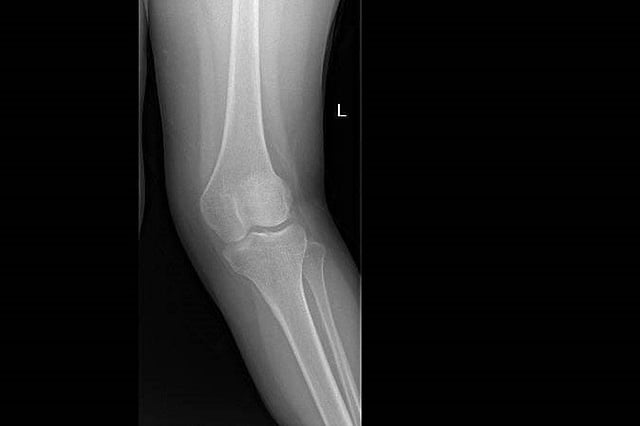

نجح فريق طبي في قسم جراحة العظام والتخدير والعمليات بمستشفى الملك خالد ومركز الأمير سلطان للخدمات الصحية بالخرج، بقيادة الاستشاري خالد سليمان، في إنهاء معاناة فتاة سعودية تعاني من تشوه في الركبة اليسرى واعوجاج خارجي (ركبة فحجاء) وعرج عند المشي.

وتم استقبال المريضة في عيادة العظام، وبعد عمل الأشعة المطلوبة والفحوصات اللازمة، وُضعت خطة علاجية من قبل الفريق الطبي المعالج وأجريت العملية للمريضة باستخدام تخدير نخاعي (نصفي)، وتم إصلاح اعوجاج عظمة الفخذ وعظمة الساق والتشوه بالركبة اليسرى، وتكللت العملية بالنجاح.